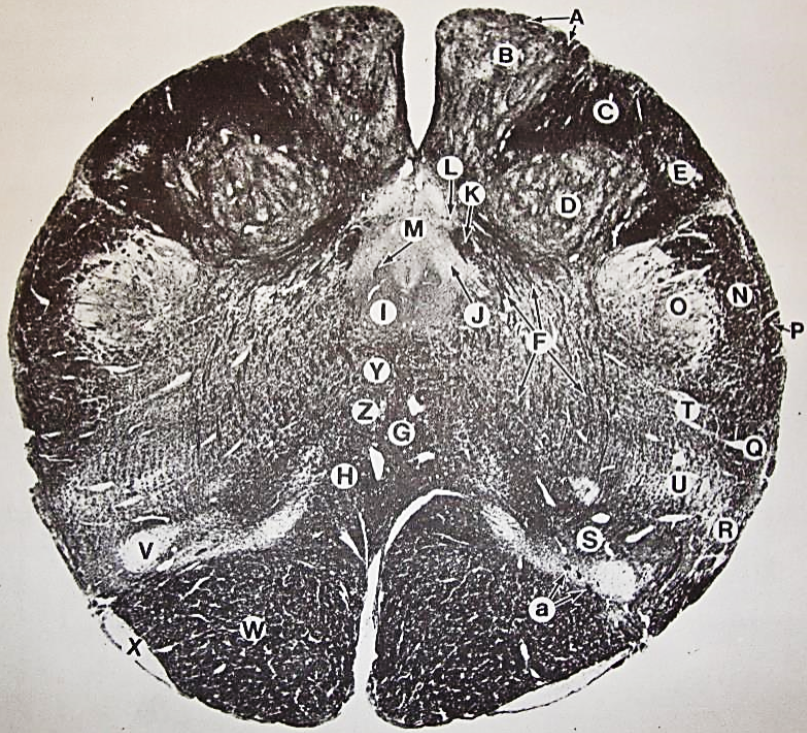

A

Fasciculus gracilis

B

gracile nucleus

C

fasciculus cuneatus

D

cuneate nucleus

E

spinal trigeminal tract

F+G collectively

spinal trigeminal nucleus

H

accessory nucleus

I

pyramidal decussation

J

rubrospinal tract

K

posterior spinocerebellar tract

L

anterior spinocerebellar tract

M

lateral spinothalamic tract

N

anterior spinothalamic tract

O

lateral vestibulospinal tract

P

medial longitudinal fasciculus

Q

tectospinal tract